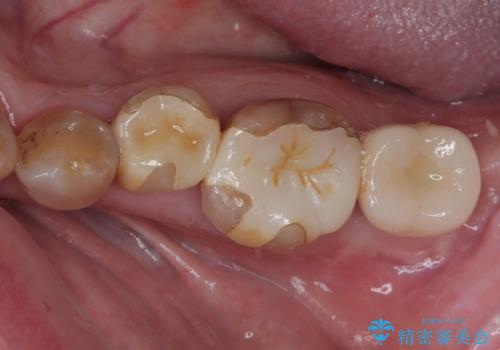

左下はインプラントによる補綴治療を行いました。

左上の小臼歯は根尖病巣が大きかったため、今後も定期的にレントゲンを撮り、経過観察していく予定です。